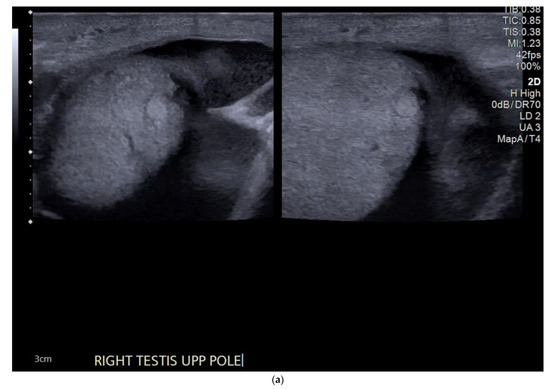

4.1. Seminomatous Germ Cell Tumour

4.2. Non-Seminomatous Germ Cell Tumour (NSGCTs)

| Seminomas | Homogenous and hypoechoic Well circumscribed Occasionally contain cystic components or calcifications |

| Non-seminomas | Heterogenous Irregular margins Cystic and calcification components seen commonly |